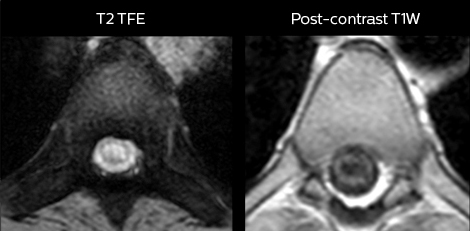

in image acquisition and postprocessing algorithms.”“mDIXON TSE sequences allow simultaneous characterization of morphological changes from the in-phase T2-weighted images and visualization of edematous changes, thanks to the water T2-weighted images from the same acquisition. Anatomical and morphological considerations could be a partial or complete ligament tear, a bony avulsion or hematoma.” “For soft tissue assessment mDIXON brings similar benefits. For example in one T2-weighted mDIXON TSE acquisition, having the multiple contrasts helps us assess abnormalities in peripheral nerves fascicles, which may be due to anatomical or inflammatory changes..” “In peripheral joints, we get good image quality in difficult areas with mDIXON TSE. Fat suppressed images appear homogeneous over the entire image, even with large coverage at 3.0T – for instance in scapular or hip girdles – or in the bearing areas or around metal prostheses*, where fat suppression is often deficient with STIR or spectral fat suppression, causing diagnostic difficulties. If a diagnostic image is right the first time, we don’t need to repeat or add a sequence.” “mDIXON TSE sequences allow simultaneous characterization of morphological changes from the in-phase T2-weighted images and visualization of edematous changes, thanks to the water T2-weighted images from the same acquisition. Anatomical and morphological considerations could be a partial or complete ligament tear, a bony avulsion or hematoma.” “For soft tissue assessment mDIXON brings similar benefits. For example in one T2-weighted mDIXON TSE acquisition, having the multiple contrasts helps us assess abnormalities in peripheral nerves fascicles, which may be due to anatomical or inflammatory changes..”

“We use mDIXON TSE extensively in our spine imaging in the emergency room,” says Dr. Karis. “It’s particularly nice in that it is very robust with regard to susceptibility type of problems that would come up with traditional spectral fat-saturated images; these problems are essentially eliminated with the mDIXON technique. In our ED environment it’s really nice to have the fat-free imaging that goes along with the mDIXON technique.

“For the thoracic and cervical spine routine non-contrast exam, for example, we perform one mDIXON T2 TSE sequence, which provides us with two outputs: the fat-and-water-together T2-weighted images, as well as the water-only sagittal T2-weighted images. And then we also perform an axial gradient echo exam.”